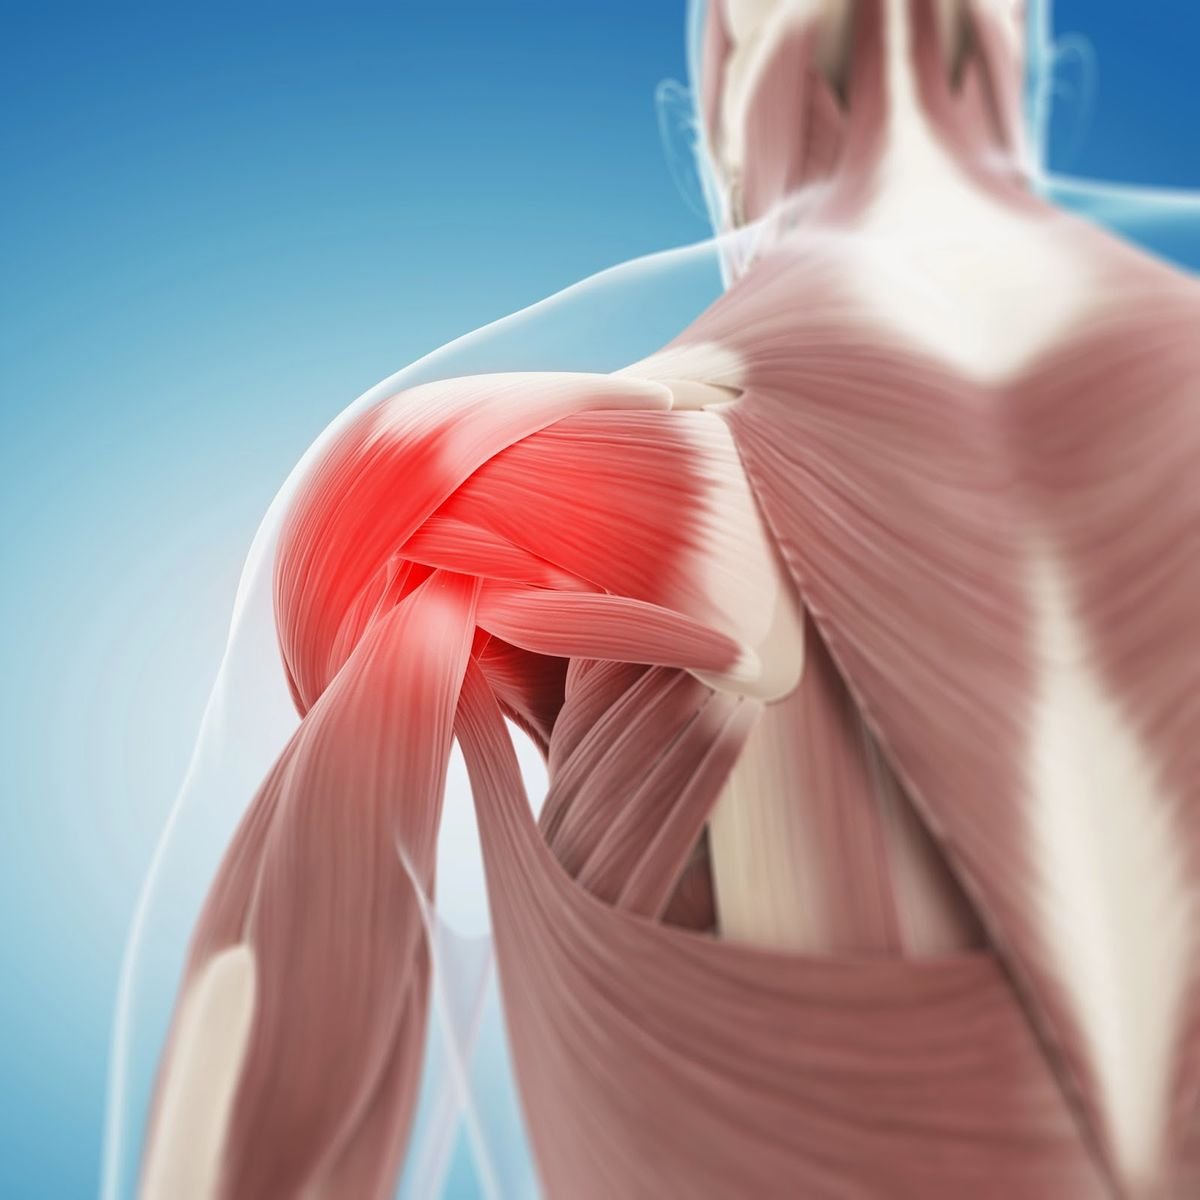

Frozen shoulder causes stiffness and pain; physiotherapy and exercises help restore mobility.